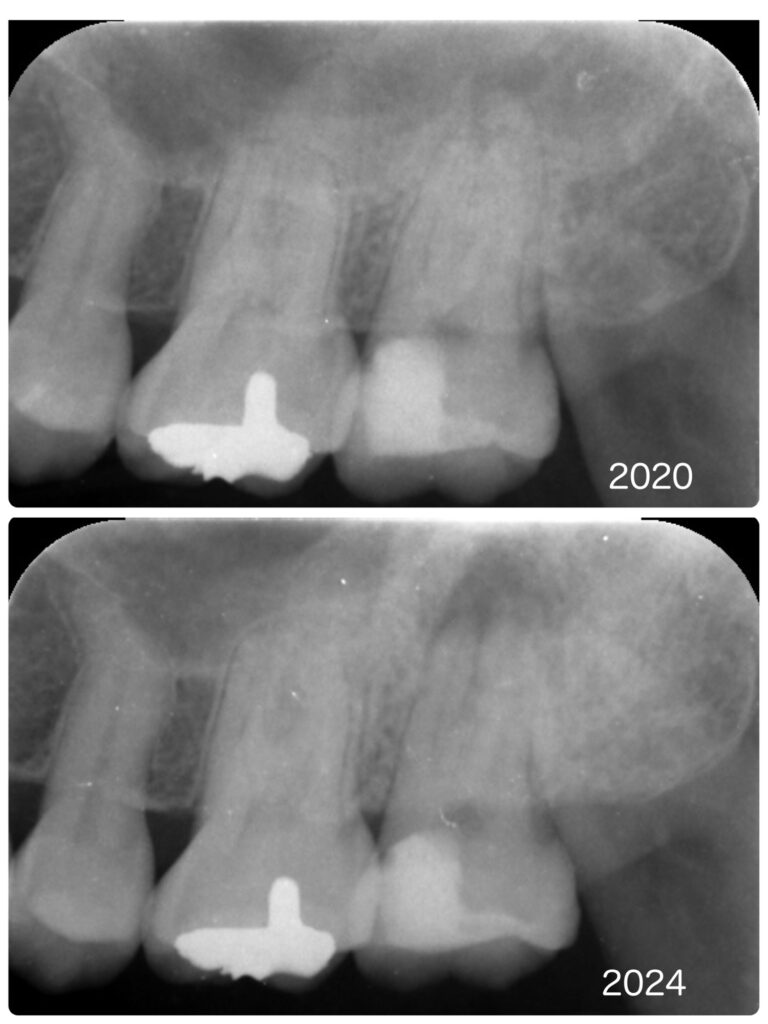

この患者様は2020年の初診時に左上の最後臼歯の根の先に小さな根尖病変の存在が疑われました。しかし、症状もなく他院で装着した自由診療のセラミッククラウンも入っていたため、本人の希望もあり経過観察をしていました。

その後、数年ぶりにお越しの際、歯肉におでき(フィステル、サイナストラクト)が認められ撮影したレントゲンで根尖病変が大きくなっていたので、自覚症状はないようでしたがご説明を差し上げ、治療を開始しました。